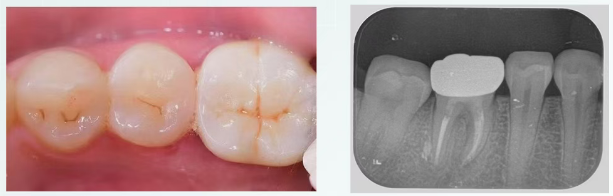

4个月复查

戴牙四月复查,可见修复体及牙周情况良好,

正常行使功能,日常使用无异常。

8个月复查

治疗术后八月复查,糊剂固化稳定,

根分叉处及牙周膜影像较术后两月有明显改变。